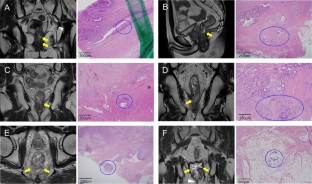

Fig. 1

Fig. 2

Fig. 3